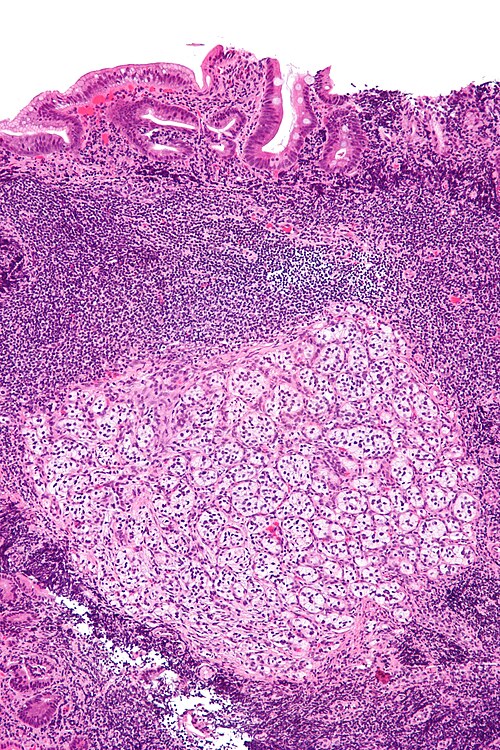

Clinical history

35 year old man, duodenal mass.

Low magnification. H&E stain.